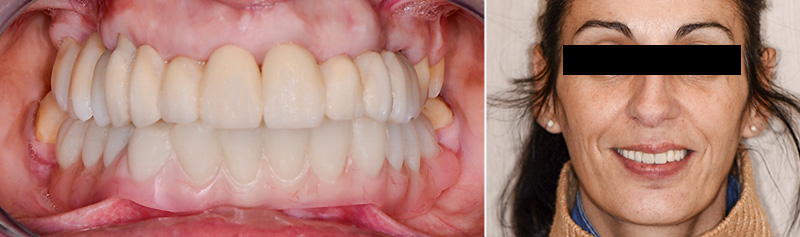

Les restaurations finales maxillaires ainsi que les chapes mandibulaires ont été essayées et assemblées à l’aide d’un CVIMAR. Après assemblage des chapes porteuses d’attachements, les prothèses amovibles d’usage ont été essayées puis délivrées à la patiente.

Pour garantir une bonne fonction, une occlusion bilatéralement équilibrée a été mise en place. Une période de 15 jours a été respectée avant le scellement des parties femelles dans l’intrados de la prothèse maxillaire.

Fig. 12 : assemblage des prothèses d’usage.